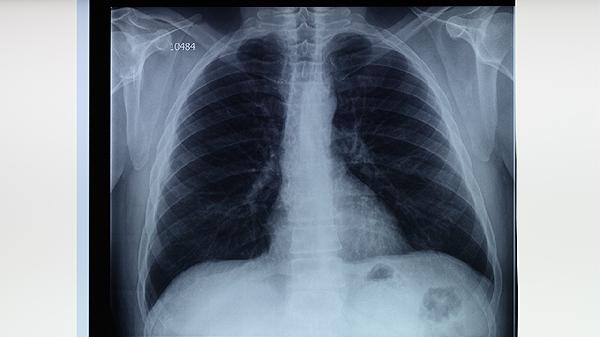

胸部X線檢查可發(fā)現(xiàn)典型的上葉尖后段或下葉背段浸潤影、空洞形成等肺結(jié)核特征性表現(xiàn)。CT檢查能更清晰顯示微小病灶和早期病變,對肺外結(jié)核的診斷也有重要價(jià)值。支氣管鏡檢查可直接觀察氣道病變并獲取活檢標(biāo)本,適用于痰檢陰性但高度懷疑肺結(jié)核的患者。分子生物學(xué)檢測如GeneXpertMTB/RIF可快速檢測結(jié)核分枝桿菌及其利福平耐藥性,具有高敏感度和特異性,但需要專業(yè)設(shè)備支持。病理學(xué)檢查通過組織標(biāo)本發(fā)現(xiàn)干酪樣壞死和朗格漢斯巨細(xì)胞可確診結(jié)核,但屬于有創(chuàng)檢查。